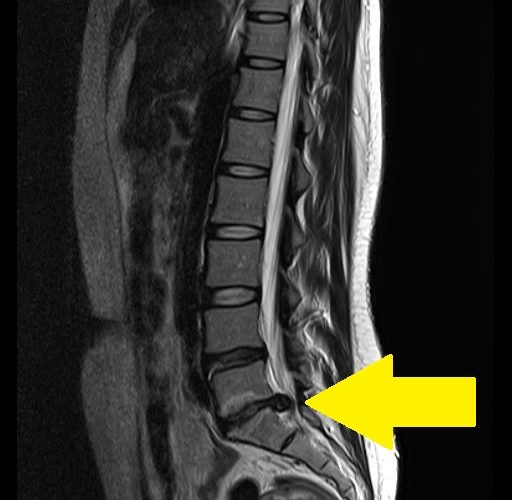

- MRI : 디스크의 위치와 상태를 정확하게 보여줍니다.